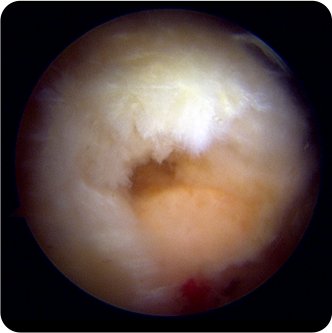

회전근개파열의 여러 모습들

회전근개파열은 성인의 어깨에 발생하는 만성 통증의

가장 큰 원인으로 어깨 관절을 싸고 있는 회전근개의

염증 또는 퇴화로 인해 어깨힘줄이 파열된 상태를 말합니다.